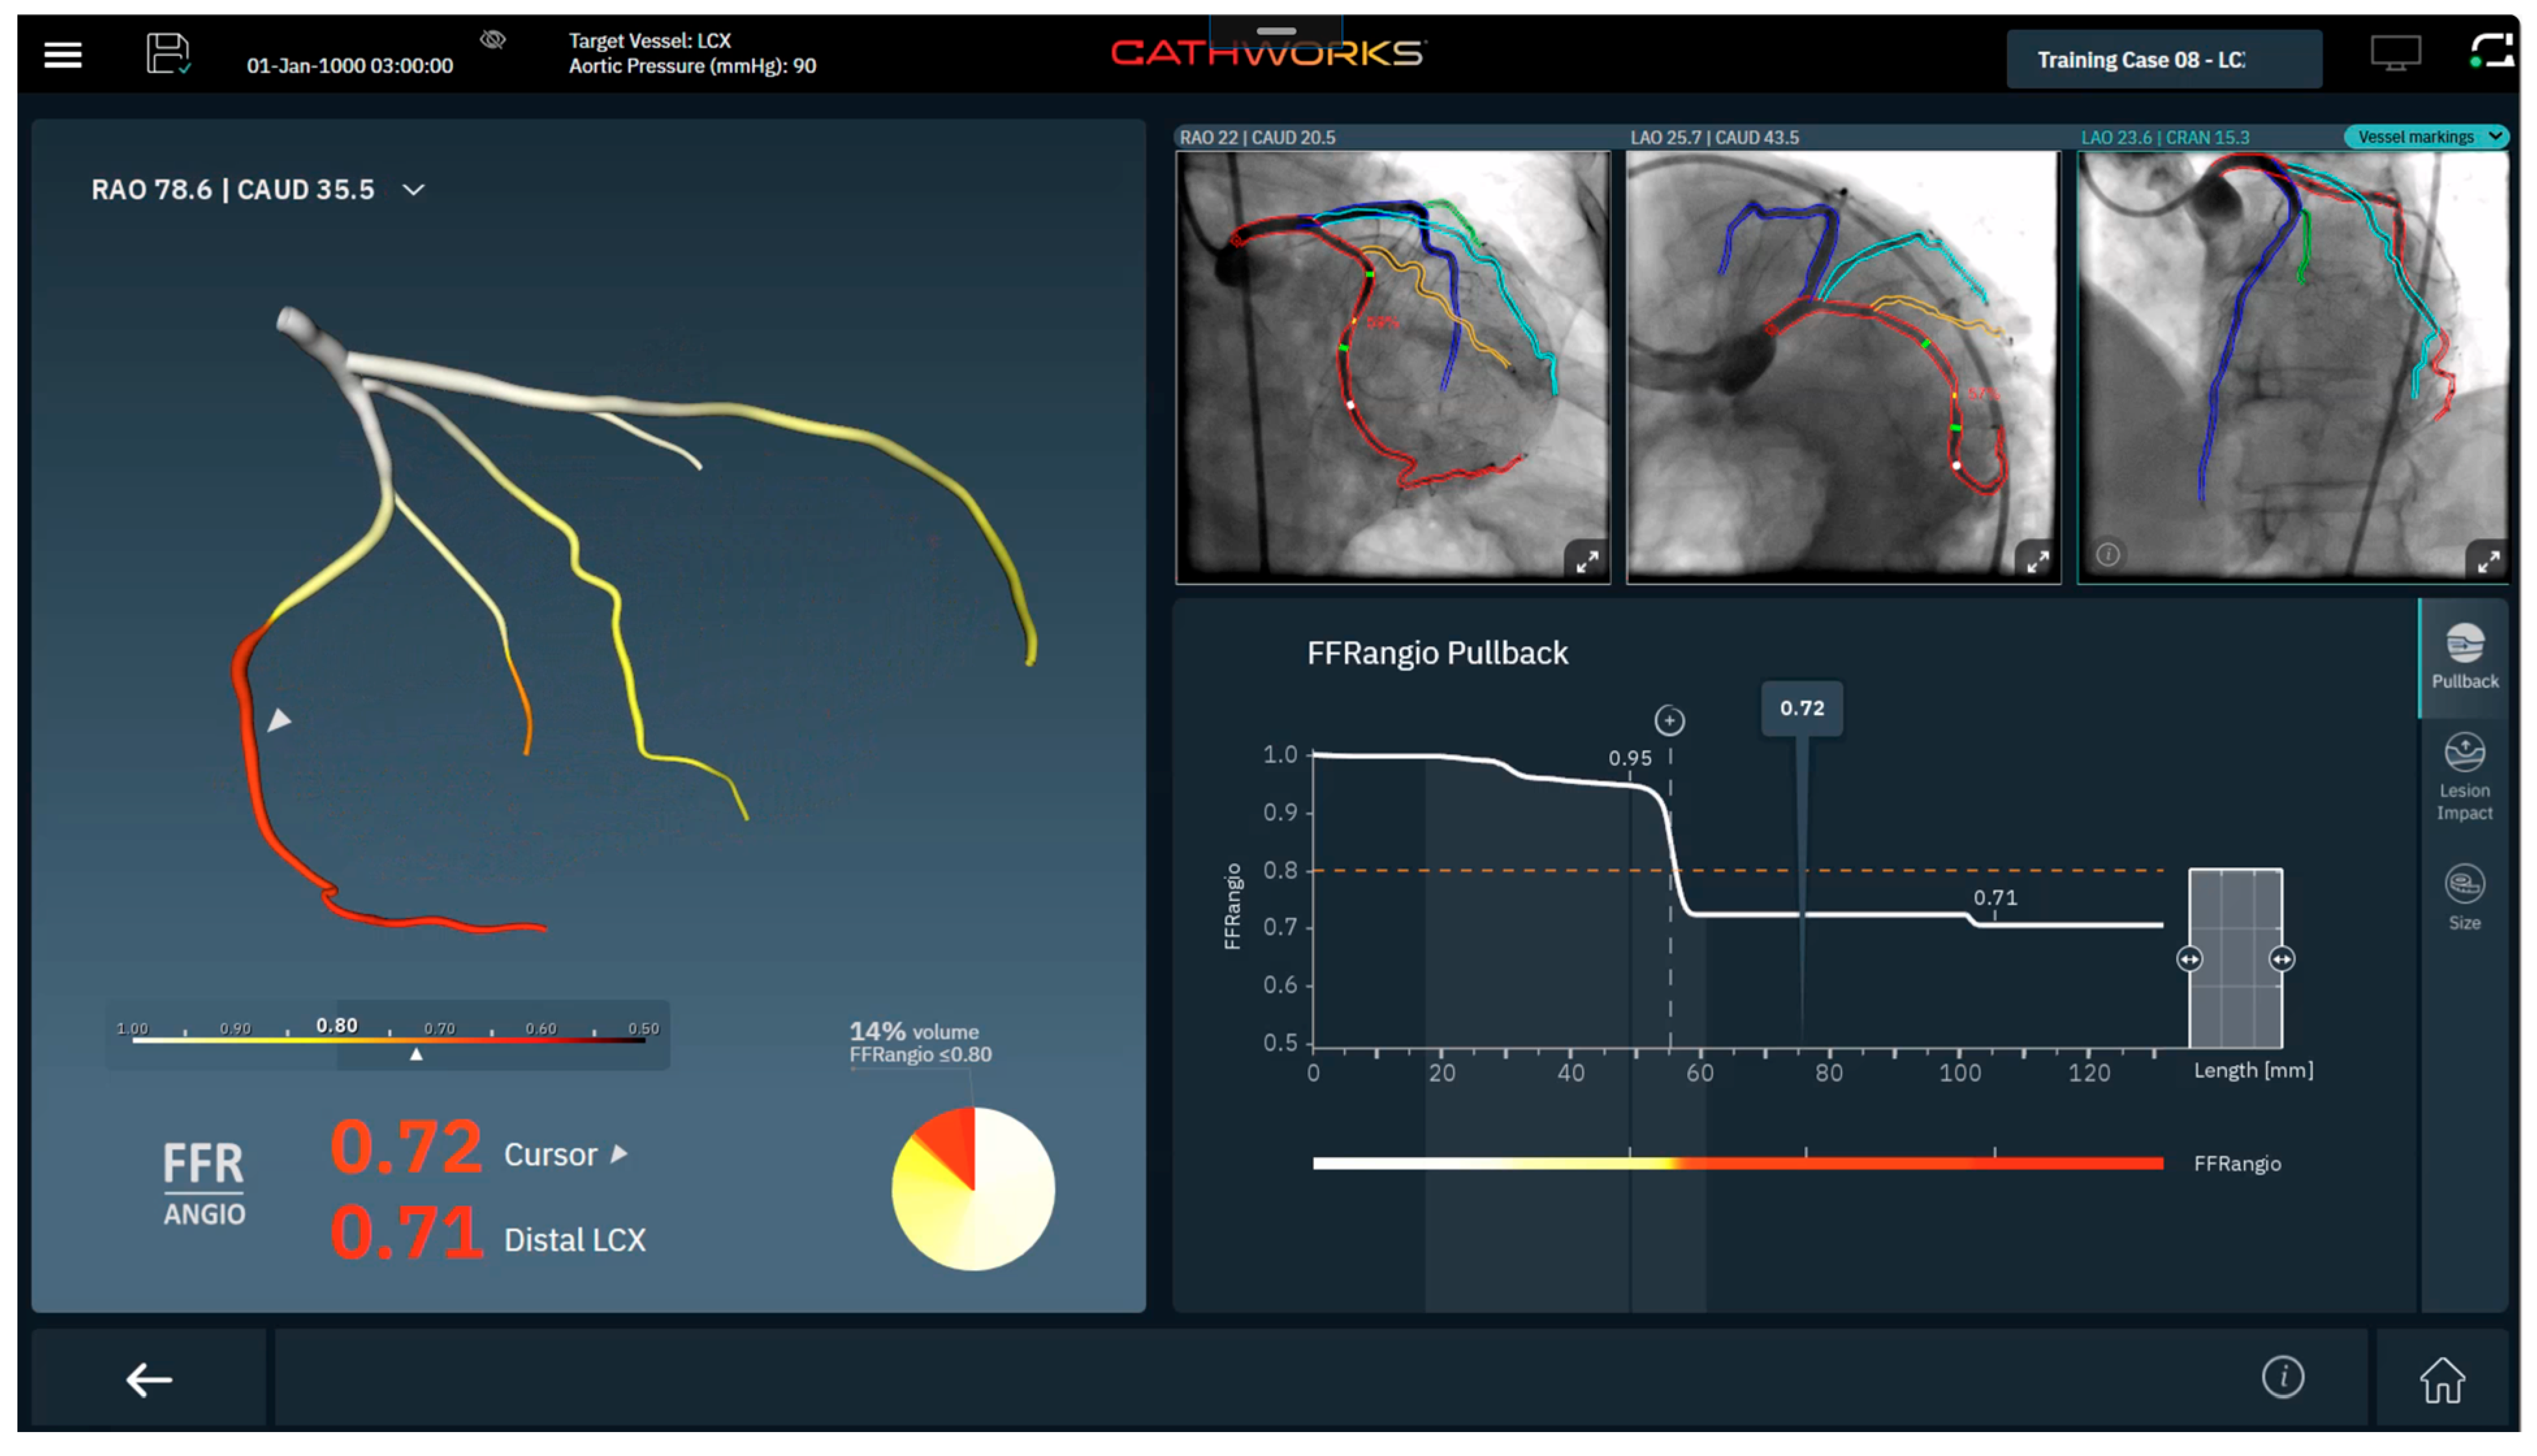

FFRangio uses a proprietary flow resistance analysis algorithm to conduct multivessel analysis [20] (Figure 4). This technology requires three angiographic views separated by at least 30 degrees, reporting FFRangio values along the coronary tree. Recent software upgrades add (I) pullback analysis to determine lesion-specific contributions to flow limitation, (ii) a lesion impact tool to estimate relative change in flow with stent placement, and (iii) vessel-sizing to estimate lesion length and vessel size [21].

Figure 4. Example of FFRangio Output Interface (Reprinted with permission Ref. [21]. Copyright 2025 CathWorks).